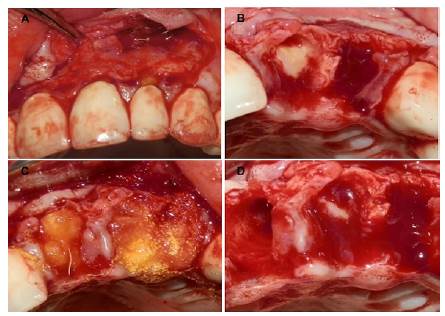

Teniendo en cuenta los hallazgos clínicos y radiográficos se diagnosticaron abscesos periapicales, con mal pronóstico, por lo cual se realizó la cirugía de extracción de los órganos afectados (Figura 2 A, B). En el momento quirúrgico se observó un tercer órgano afectado por lo que, también se hizo necesario hacer la extracción de la pieza dentaria. Posterior a esto, se realizó la biomodificación de los alveolos con tetraciclina diluida (Figura 2 C,D).